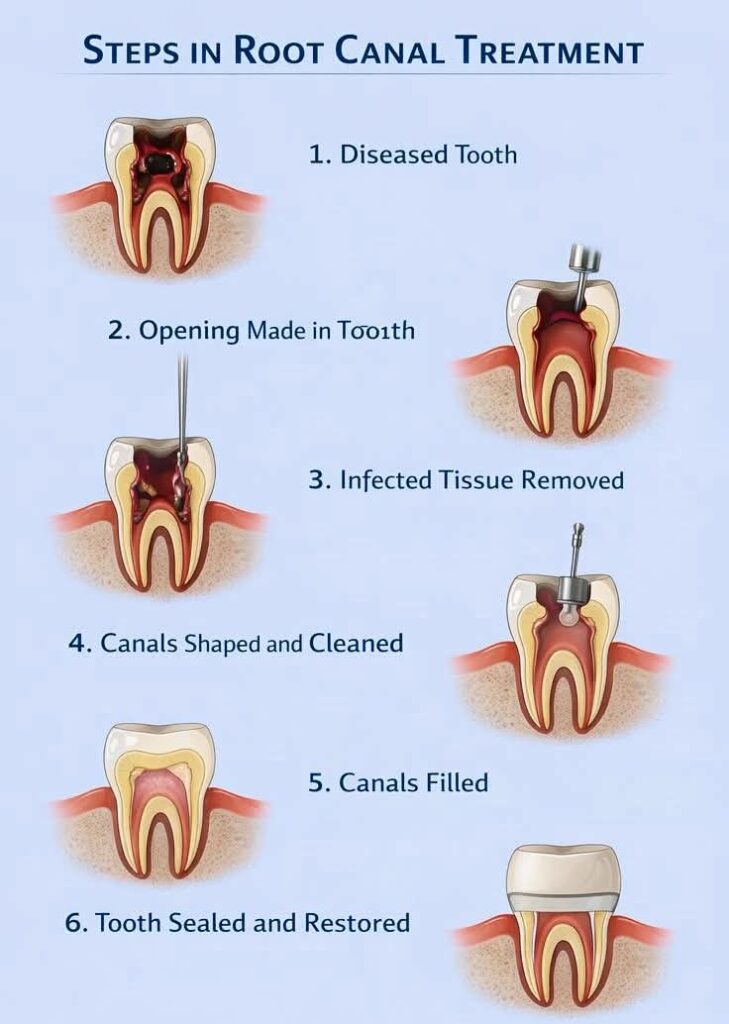

What Is Root Canal Treatment (RCT)?

Root canal treatment (RCT) is a dental procedure that removes infected pulp from inside the tooth, cleans the root canals, and seals them to prevent further infection, saving the natural tooth.

RCT helps eliminate infection, relieve tooth pain, and restore normal function without removing the natural tooth. Our experienced dentists ensure safe, comfortable, and effective treatment with long-lasting results.